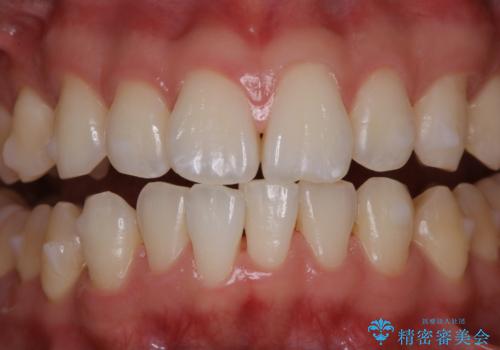

インビザラインでのマウスピース矯正中にPMTC

- インビザライン矯正治療中の方です。アタッチメントの周りの汚れが気になるとのことで、PMTC30分コースを行いました。